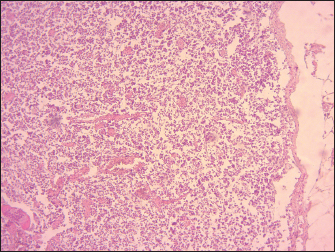

The lymphoid follicles in Peyer’s patches exhibited destruction, characterized by lympholysis (Fig. 6). MLNs showed severe congestion, hemorrhage, swelling, and depletion of lymphoid cells (Fig. 7). Additionally, other lesions are marked by the depletion of lymphocytes in the spleen, and histopathological changes in the heart, including congestion and hemorrhages. The thymus showed severe depletion of lymphocytes and severe congestion (Fig. 8). Furthermore, the liver showed severe congestion and hemorrhage with hepatocyte atrophy accompanied by the expansion of the sinusoidal spaces. The kidney exhibited slight glomerular atrophy, significant necrosis, and loss of epithelium in the renal tubules.

Fig. 7. Sheep, MLNs demonstrating severe lymphoid depletion mainly in the cortex with congestion and severe hemorrhage (100X, H&E).

The results of the histopathological study revealed lympholysis and loss of lymphoid cells in Peyer’s patches, spleen, thymus, and lymph nodes of lambs affected by PPR.

The lymphoid depletion observed in the present study can be attributed to a combination of direct viral cytopathic effects. These include the replication of PPRV within lymphocytes, which results in direct damage and death of these cells, and the immunosuppression resulting from lymphoid depletion predisposes the host to secondary infections, which can further destroy and deplete lymphoid tissues.